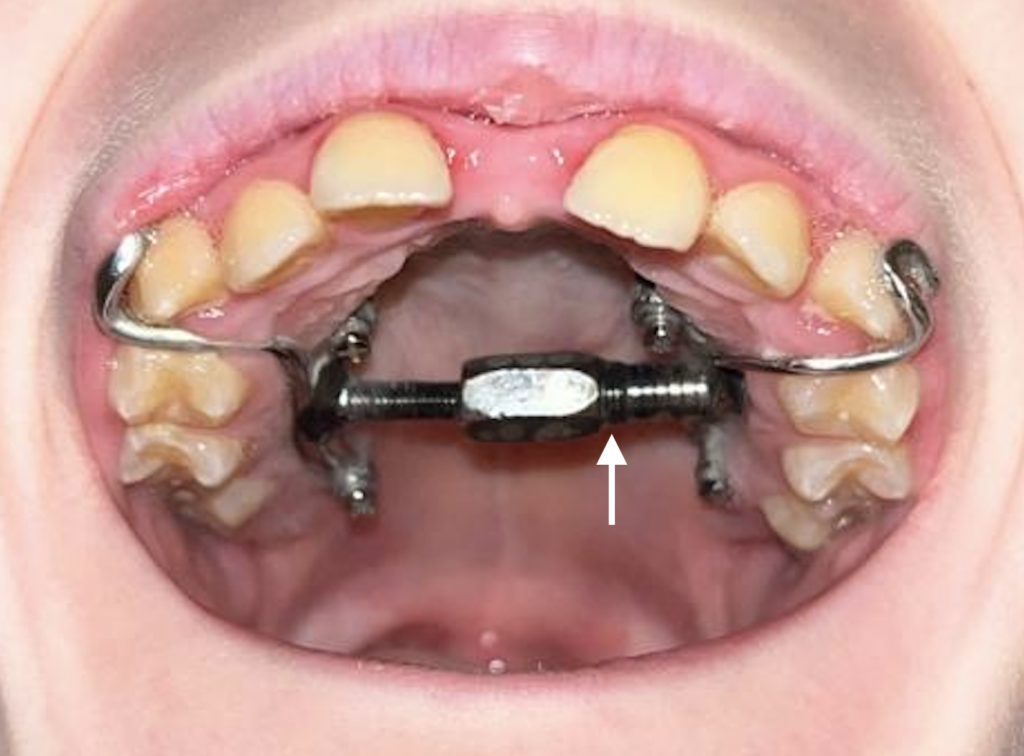

Per garantir la bona evolució del tractament seguiu el ritme indicat per la Dra: 2 activacions al dia (matí i nit)

2. COM REALITZAR LES ACTIVACIONS: